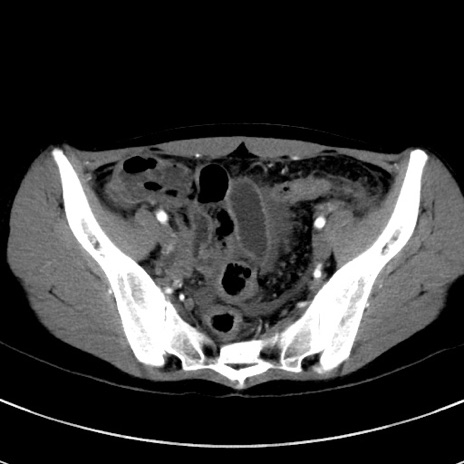

冠状断像

【症例】20歳代女性

【主訴】嘔吐、下腹部痛

【現病歴】昨日夕食後に嘔吐し下腹部痛が出現。本日になっても嘔吐持続し改善しないため来院。

【身体所見】意識清明、BT 37.2℃、BP 108/67mmHg、腹部:平坦、やや硬、下腹部正中から右にかけて圧痛あり、反跳痛軽度あり、tapping pain(+)。

【データ】WBC 13600、CRP 14.94